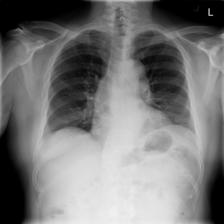

While these resources enable large-scale model development and benchmarking, they are also known to exhibit critical challenges that complicate clinical translation. The most notable problems are imperfect labels derived from automated text mining approaches [16, 17], demographic and institutional biases that induce domain shift [18, 19, 20], and evaluation protocols that do not reliably reflect clinical operating points [21, 22]. Collectively, these factors can produce deceptively high internal performance that does not persist under external validation [23]. Automated report mining has enabled dataset curation at scale for datasets such as CheXpert, MIMIC-CXR, ChestX-ray14, and PadChest, but remains vulnerable to negation, uncertainty, and study-level misalignment, leading to false positives/negatives and label drift across conditions and sites [24]. Such noise is sufficient for training, yet it constrains model reliability when radiologist consensus is the standard. An example case of automated labelling leading to a false positive for Pneumonia is shown in Figure 1. Most large public datasets originate from single centres or health systems and differ in populations, acquisition hardware, protocols, and preprocessing. Models can therefore exploit site-specific artefacts (e.g., devices, overlays, or processing fingerprints) rather than pathologies, yielding performance that collapses when scanners or workflows change [25, 26]. While AUROC and related metrics are useful and widely adopted for ranking classifiers, they obscure clinically meaningful operating points and the asymmetric costs of false positives versus false negatives [21, 22]. Under class imbalance, AUPRC and threshold-dependent metrics (Sensitivity, Specificity, F1) are more informative [27], but only when decision thresholds are specified and validated appropriately. In this study, we make the following contributions:

Refer to caption

Figure 1: Example radiography report from the MIMIC-CXR dataset. The associated chest radiograph is labelled as Lung Cancer and Pneumonia by the automated CheXpert labeller. Pneumonia indicators (red) are negative mentions, leading to a false diagnosis.